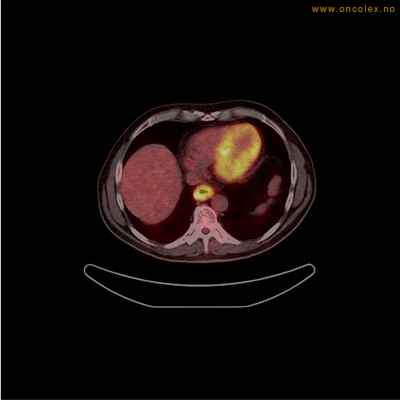

Vev som tar opp mer radioaktivt stoff, synes som hvite områder som lyser opp mer i forhold til annet vev som tar opp mindre sukker.

Spredningssvulster til lever med sentral nekrose.